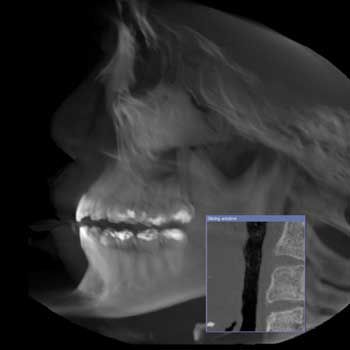

Dental X-rays are diagnostic tools that create detailed images of your teeth, gums, and jaw. Dr. Yeo and Dr. Tan use these images to detect issues invisible to the naked eye, such as cavities between teeth, bone loss and impacted wisdom teeth. At Yeo Family Dental Group, we offer digital X-rays and advanced Cone Beam CT scans to provide comprehensive care tailored to your needs.

Dental CBCT images provide three-dimensional (3-D) information rather than the two-dimensional (2-D) information provided by a conventional X-ray image. This may help with the diagnosis, treatment planning, and evaluation of certain conditions.

During a cone beam CT examination, the C-arm or gantry rotates around the head in a complete 360-degree rotation while capturing multiple images from different angles that are reconstructed to create a single 3-D image. The X-ray source and detector are mounted on opposite sides of the revolving C-arm or gantry and rotate in unison. In a single rotation, the detector can generate anywhere between 150 to 200 high-resolution two-dimensional (2-D) images, which are then digitally combined to form a 3-D image that can provide your dentist or oral surgeon with valuable information about your oral and craniofacial health.